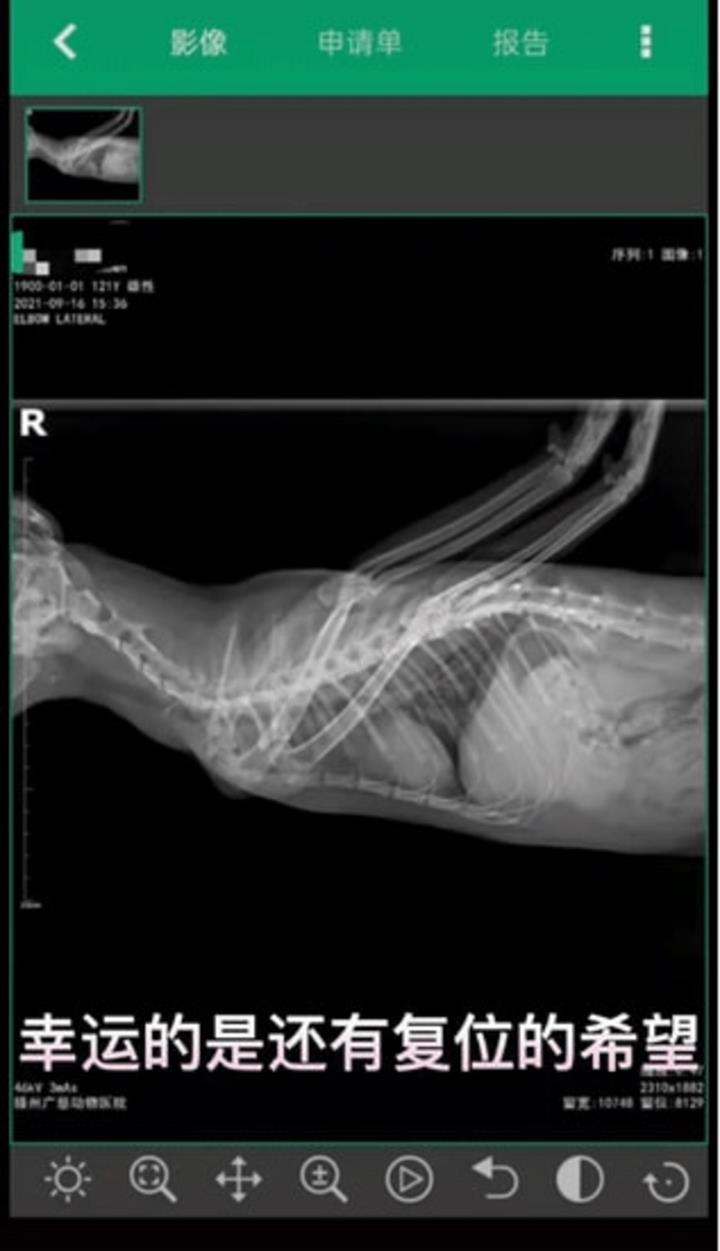

Quá trình thăm khám hoàn tất, các bác sĩ cho biết chú mèo sinh ra không bị dị tật mà vết thương này được gây ra bởi tác động của con người. Ai đó đã cố tình bẻ ngược chân của chú mèo đáng thương này ra đằng sau.

Chú mèo được đặt biệt danh là "Thiên thần" vì khuyết tật khiến hai chân trước của nó kéo dài lên trên như "một đôi cánh". "Đây là một vụ ngược đãi động vật tồi tệ và tôi hy vọng Angel sẽ không phải chịu bất kỳ đau đớn nào sau cuộc phẫu thuật”, người nhận nuôi và đưa con vật đáng thương vào viện chia sẻ.

Được biết, Angel sẽ được phẫu thuật để nắn lại đôi chân, và hiện tại con vật kém may mắn đã có được tổ ấm mới bên một người chủ ân cần, đầy tình yêu thương.